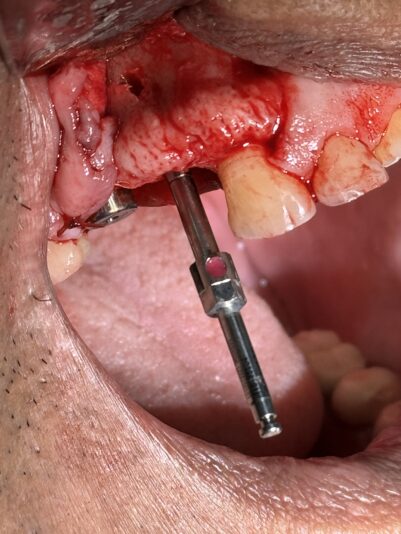

• This case was a tricky one. Sometimes, we just need to do the best with what our patients anatomy gives us. Patient was referred to me wanting an implant and there wasn’t much to work with and oh yeah, the mental foremen was smack dab in the middle of our sight.

With the help of some buccal plate decorticating, a tenting screw, and some CGF/PRF…